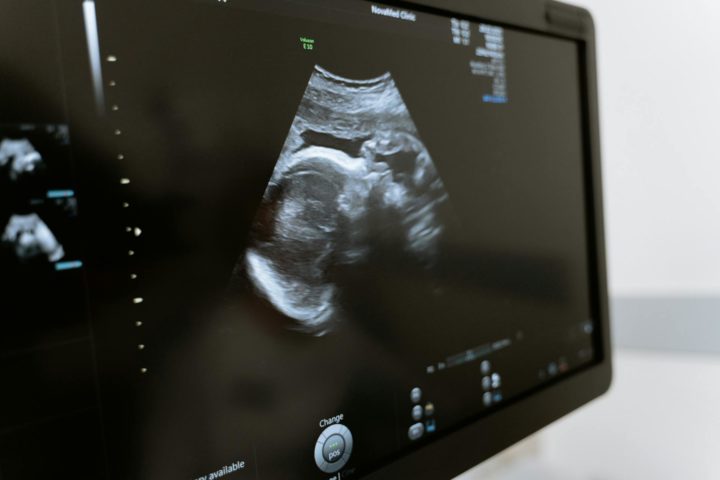

Embrião congelado em 1994 permite nascimento do ‘bebê mais velho do mundo’; entenda!